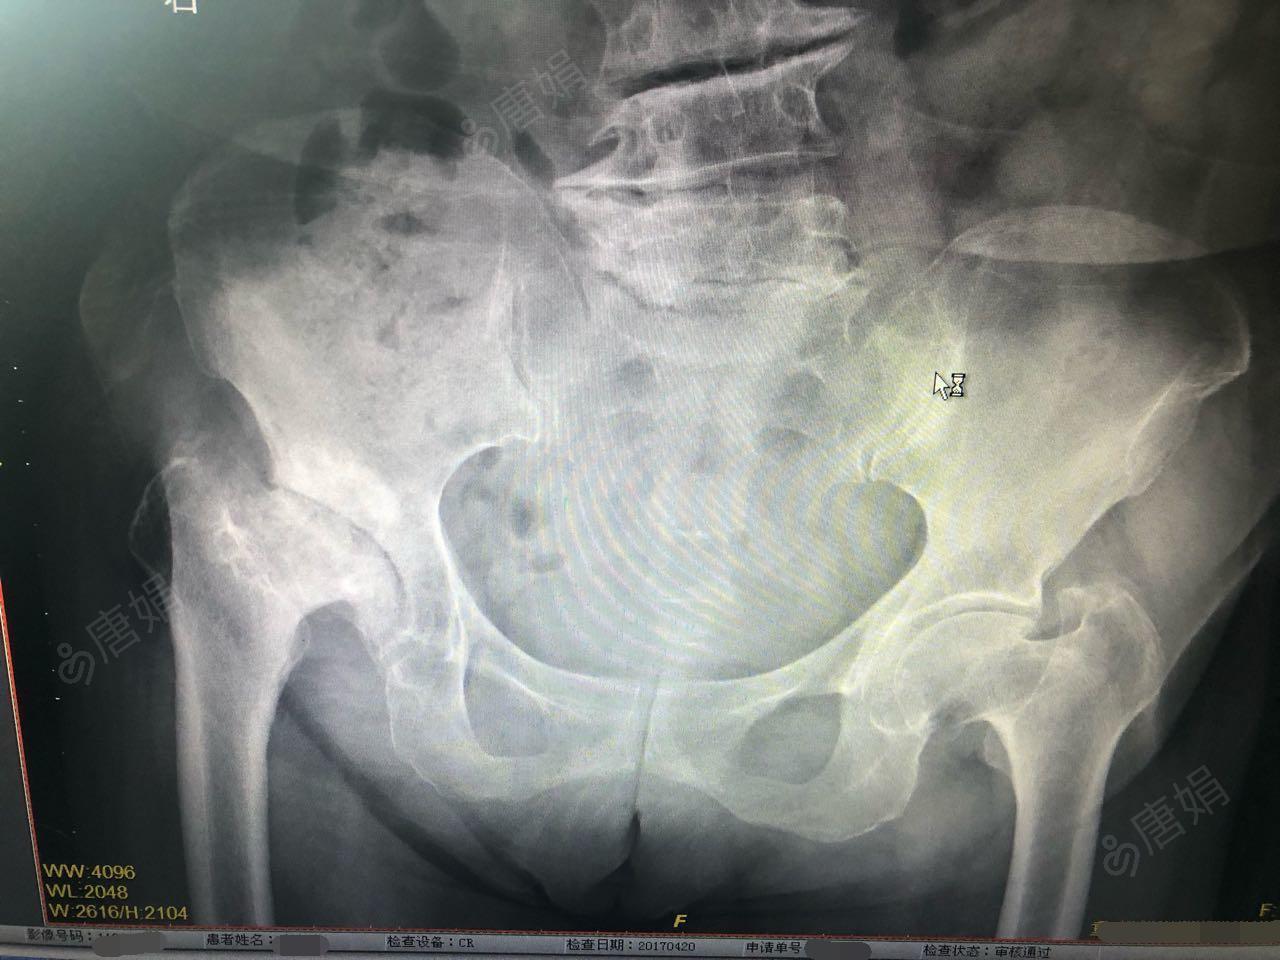

骨与关节结核(杨康平)

髋关节置换术后镇痛方案

诊断髋关节结核的试验:"4"字试验,髋关节过伸试验,托马斯(thomas)征.